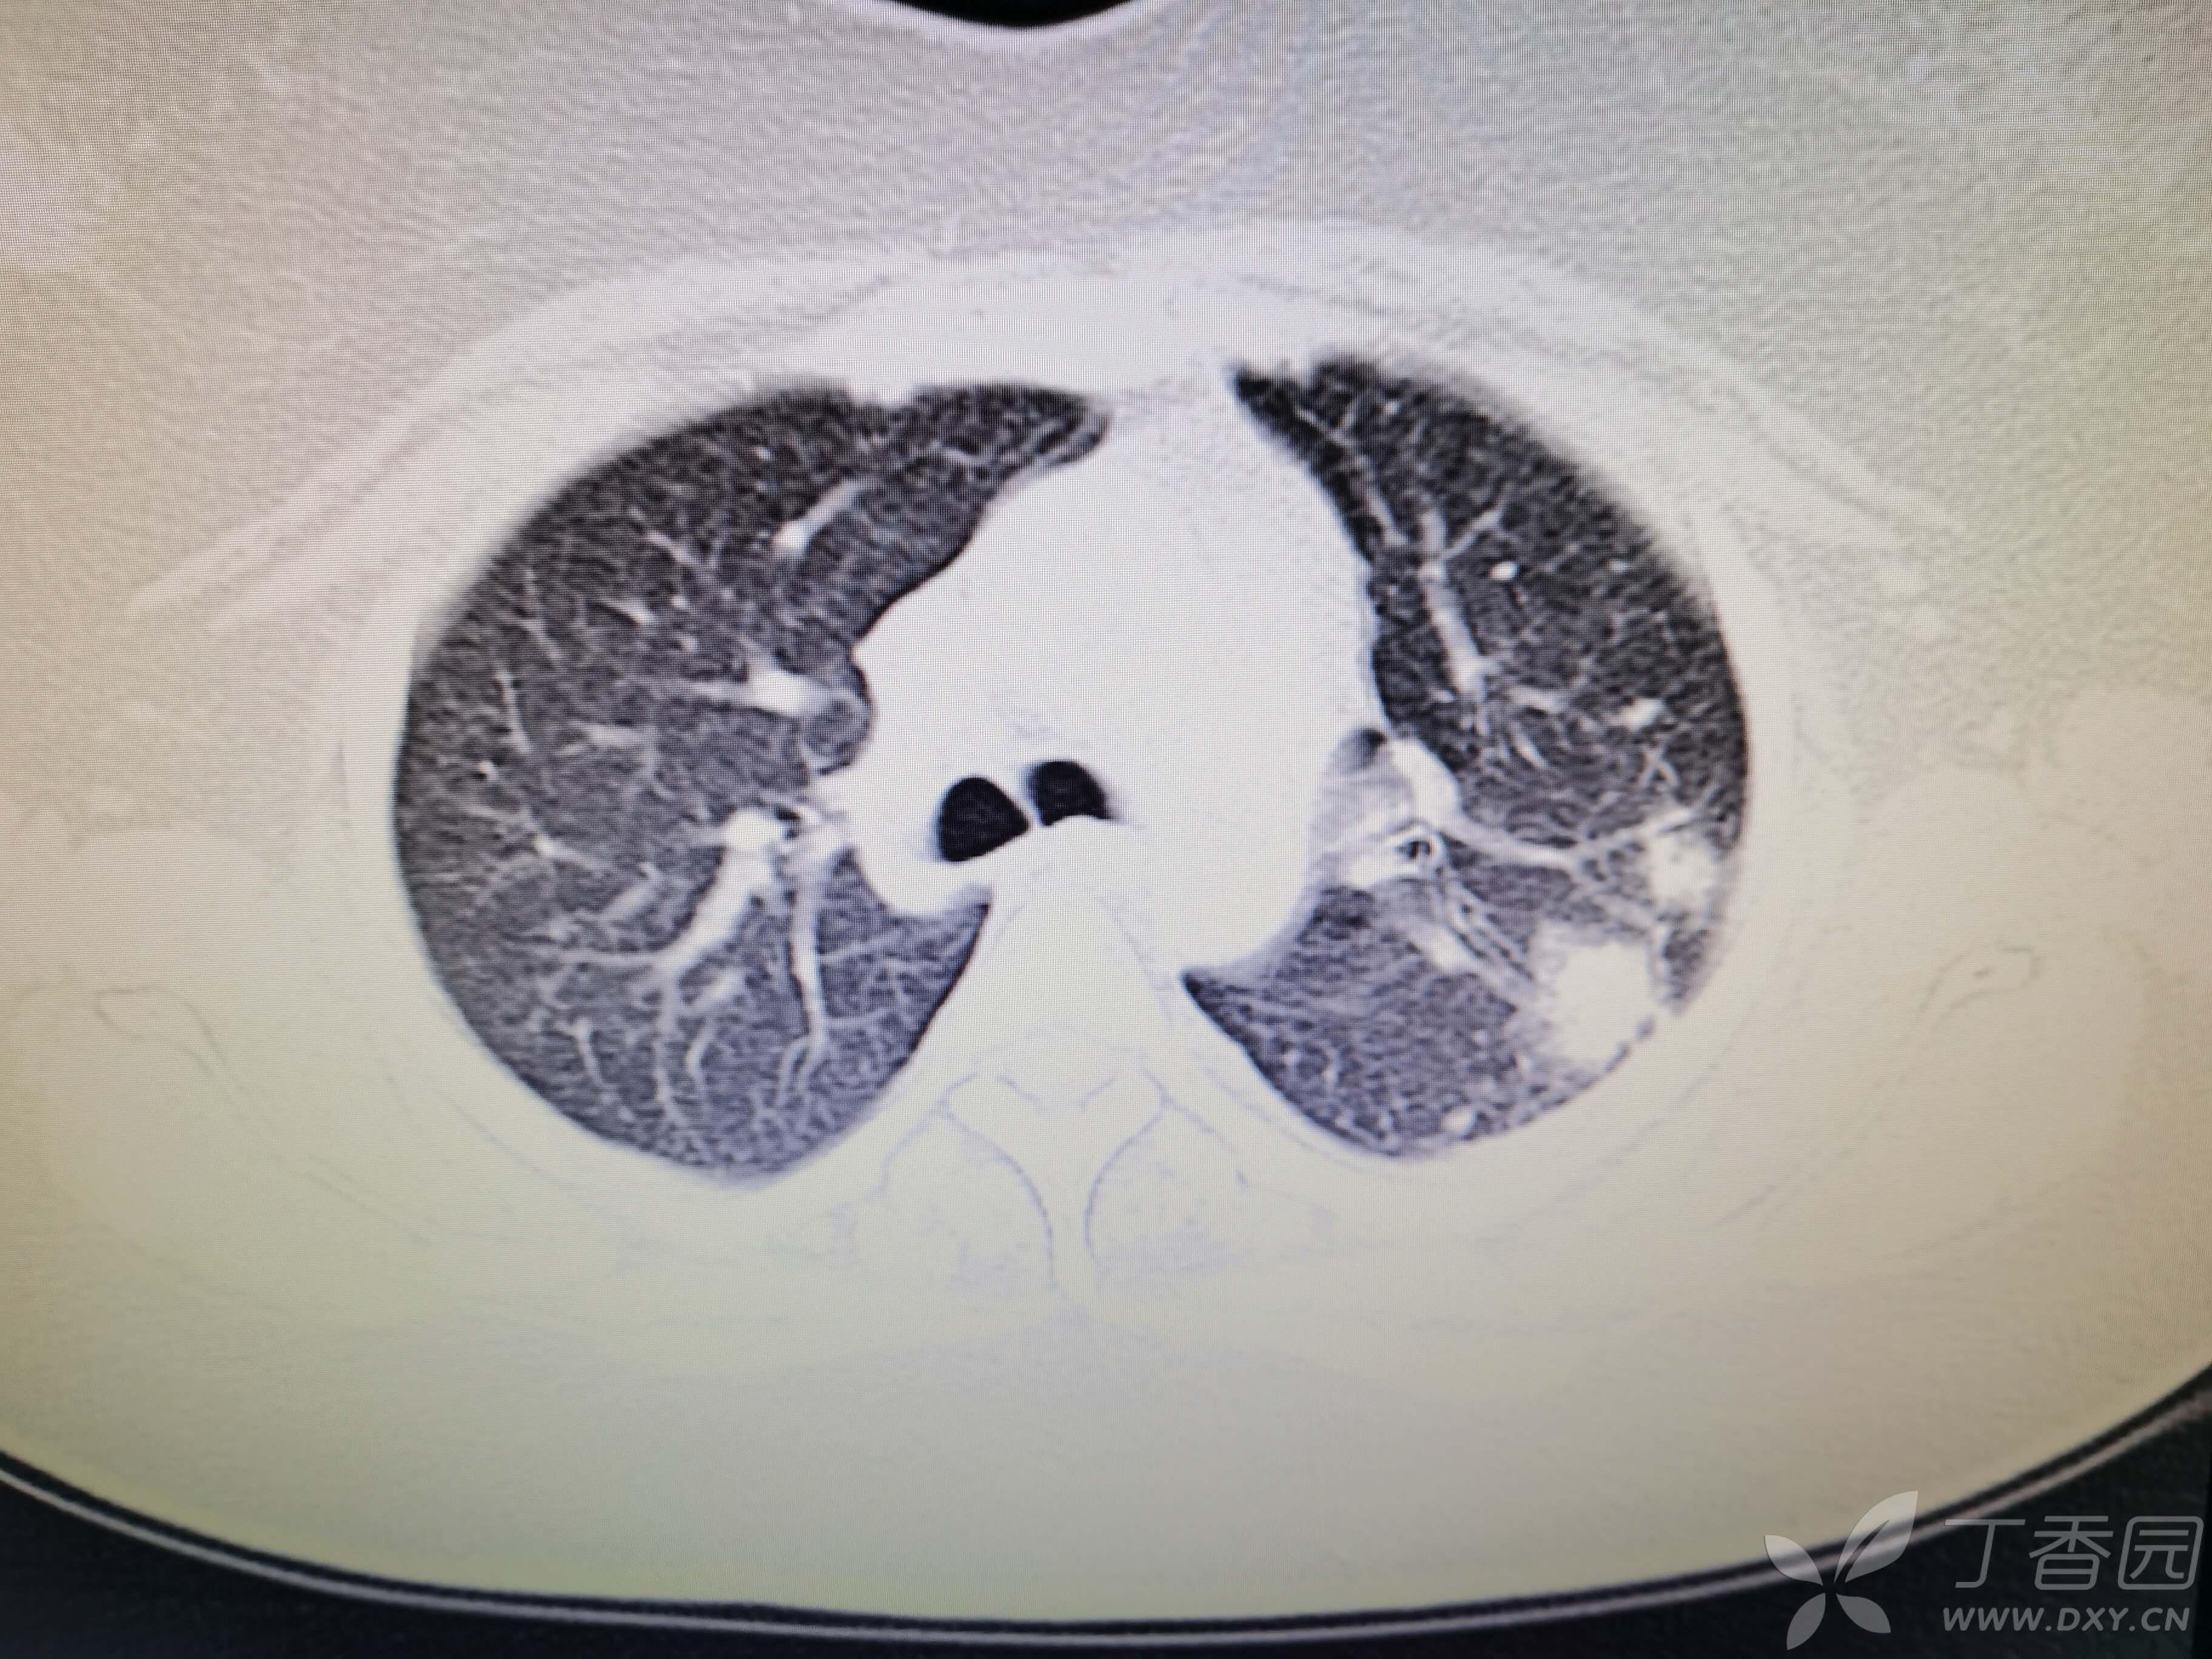

基本信息:女,三十几岁,印度人。。

胸部CT:

如题:猜肺部病灶病理。。